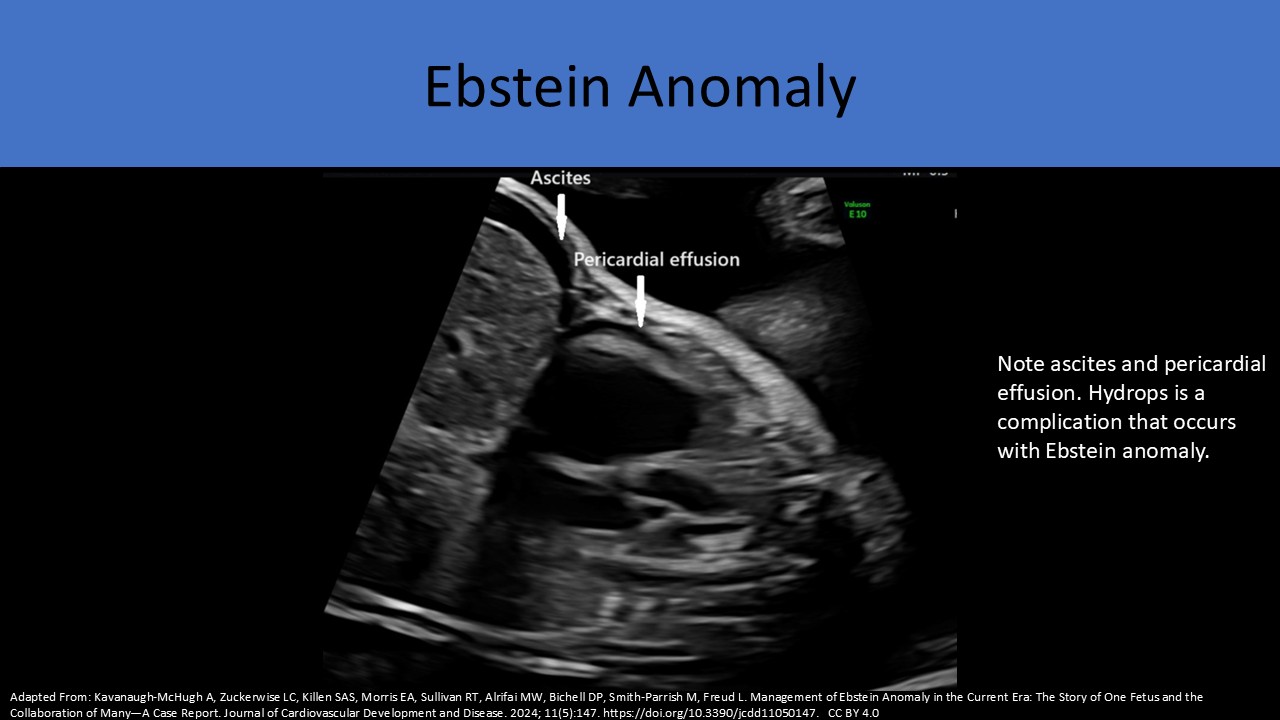

Ebstein anomaly/Tricuspid dysplasia

Ebstein Anomaly:

Ebstein Anomaly